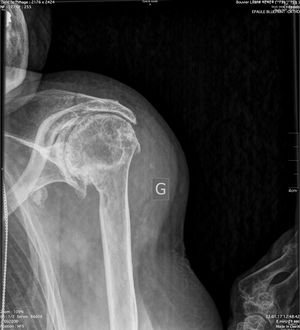

Acute proximal humerus fracture

Reverse shoulder arthroplasty is a more reliable treatment than hemiarthroplasty for complex proximal humerus fractures at least in elderly patients because its functional outcomes appear to depend less on tuberosity healing and rotator cuff integrity (Figure).[90]

Reverse shoulder athroplasty for fracture. Frontal, axial and lateral Lamy radiographs after a reverse total shoulder implant. Note the lower positioning of the glenoid baseplate, the satisfactory reconstruction of the tuberosities, and the absence of cement at the autograft level.